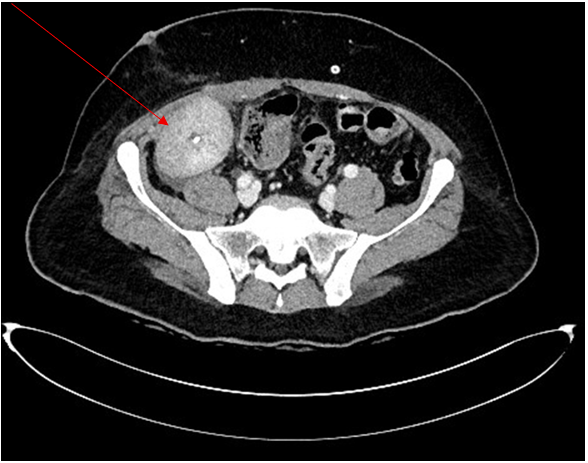

A contrast-enhanced abdominal computed tomography (CT) scan was subsequently performed to assess the renal allograft. Imaging demonstrated heterogeneous peripheral cortical enhancement of the transplanted kidney, findings suggestive of an underlying infectious or inflammatory process. Importantly, no significant abdominal fluid collections or evidence of active bleeding were identified (Figure 1). Concurrent bacterial cultures and virological screening were negative, effectively excluding alternative infectious etiologies.

Figure 1: Contrast-enhanced abdominal CT showing heterogeneous peripheral cortical enhancement of the renal allograft, consistent with an inflammatory or infectious process